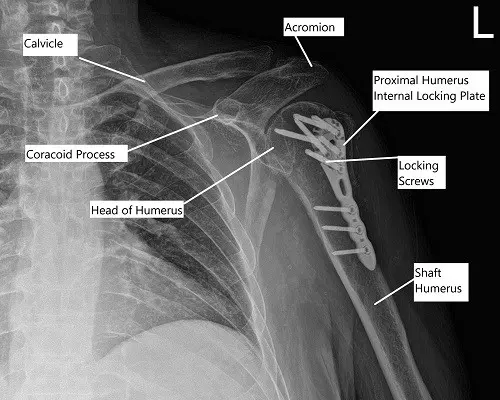

OPERATION: Open reduction and internal fixation of the left proximal humerus using proximal humerus plate and combination of locking and non-locking screws.

Post-operative x-ray of the left shoulder in AP view

A separate incision was made for reaching the distal fragment of the plate. With sharp and blunt dissection, the plate was reached and held with the sleeves. Finding the plate in an acceptable position, a K-wire was used to hold the plate in position. Fixation of the distal fragment was done with the use of one nonlocking screw and followed by fixation of the proximal fragment in a reduced position using multiple locking screws.

The fragment of the greater trochanter was also reduced with #0 FiberWire and sutured to the plate. Distal fixation was done with the use of three cortical screws. Final pictures were taken and saved in multiple positions and found to be acceptable. The wound was thoroughly cleaned and closed in layers using #0 Vicryl, #2-0 Vicryl, and Monocryl. The dressing was done using Dermabond, 4 x 4s, ABD, and Tegaderm. The patient was extubated and moved to recovery in a stable condition.